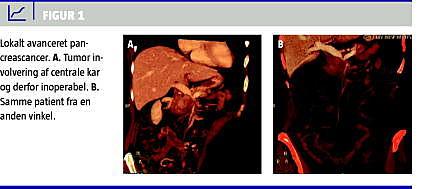

Omkring en tredjedel af alle patienter debuterer med lokalt avanceret pancreascancer (LAPC) (Figur 1 ), hvor det ikke er muligt at foretage radikal resektion, hyppigst på baggrund af indvækst i de centrale kar. Ubehandlet er den mediane overlevelse for disse patienter kun seks måneder [8]. Det er ikke afklaret, om standardbehandlingen bør være kemoterapi eller radiokemoterapi eller måske en kombination.